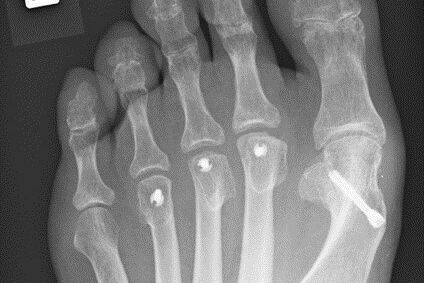

Therapie: distale Umstellung am MT1, Osteotomie an MT 2-4

Die operative Korrektur, bei der Umstellungsosteotomien an den Mittelfußknochen 1-4 links durchgeführt wurden, erfolgte im Mai 2018.

Bei anhaltenden Beschwerden wurde im Mai 2019 eine Röntgenaufnahme durchgeführt, die einen Schraubenüberstand von 1mm am Köpfchen des MT3 ergab. Dieser Befund wurde durch eine CT Untersuchung, bei der zusätzlich eine Arthrose im Grundgelenk der Großzehe und der zweiten Zehe gefunden wurde,  bestätigt.